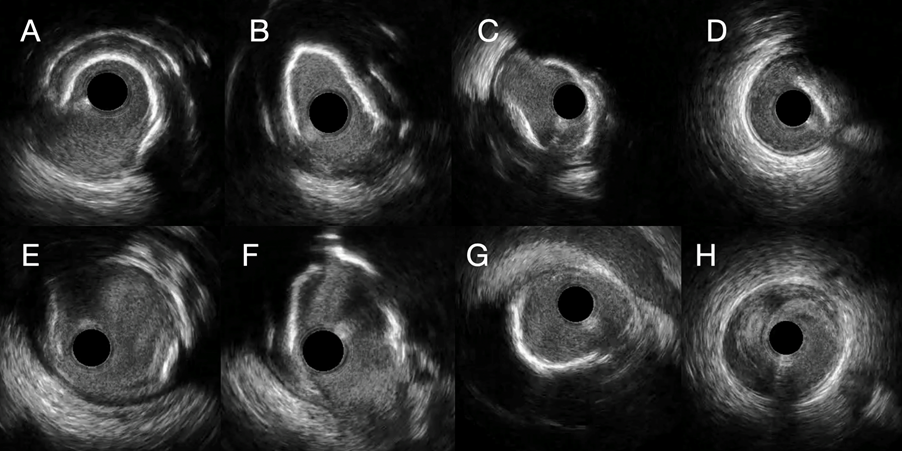

Lesion preparation is crucial in calcified CAD, as stent underexpansion due to calcification is a known predictor of target lesion failure. IVL uses sonic pressure waves to create microfractures in calcified plaques to allow more uniform plaque modification combined with balloon dilatation. In our study, all lesions were treated with IVL, achieving complete angiographic success (Figures 1 and 2). Importantly, there were no cases of lesion site thrombosis, even in these complex lesions after intensive lesion preparation and DCB alone without stent implantation.